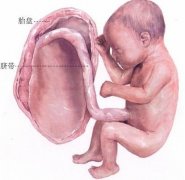

子宫颈位于子宫下部,近似圆锥体,长2.5~3 cm,上端与子宫体相连,下端深入阴道。阴道顶端的穹隆又将子宫颈分为两部分:宫颈突入阴道的部分称宫颈阴道部,在阴道穹隆以上的部分称宫颈阴道上部。宫颈的中央为前后略扁的长梭性管腔,其上端通过宫颈内口与子宫腔相连,其下端通过宫颈外口开口于阴道。

内外口之间即宫颈管。宫颈外口未生育女性呈圆形,经阴道分娩生育过的妇女呈横裂形。

宫颈的大小与宫体比例随年龄及内分泌状态等而变化。宫颈壁由黏膜、肌层和外膜组成。